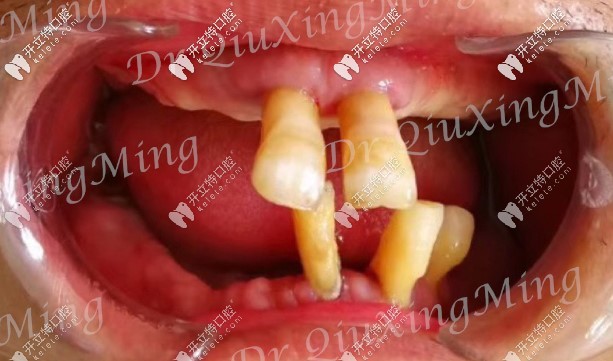

首先看下他的牙齒情況:嘴里還剩下5顆牙,還有2顆殘根,邱醫(yī)生建議全部拔掉,因為那5顆牙也已經(jīng)松動了,沒有保留的必要。

大爺口腔剩余牙齒圖